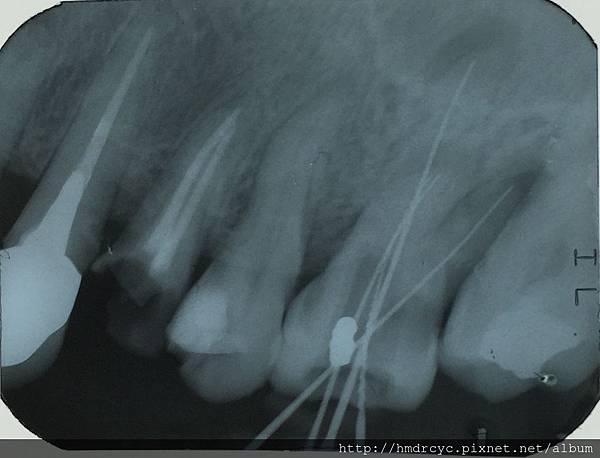

在X光上面是這樣的

X光一般病友不容易看懂

高雄欣美欣樂牙醫標示一下

只要在X光片或口腔內看到根管化膿

大概就知道這顆牙齒很難一次根管治療完成

通常要分兩到三次做

1. 第一次完成神經管清創 擴大 根管開口不封讓膿排出

2. 第二次放藥到膿包的位置 根管開口封閉

3. 第三次觀察症狀理想 完成根管封填

這顆牙齒我們一樣治療到根尖化膿的位置

牙齒內的狀況只能從X光來確認